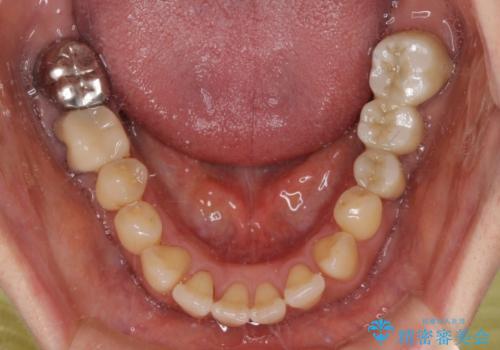

左下には新しいセラミックのブリッジが装着されていたため、ブリッジを壊さずに改善できるところまで咬み合わせを改善していくこととしました。

- 飛び出した上顎前歯と正中のズレを気にして来院された患者様です。

上顎正中が右側にずれていたので、むし歯が酷く抜歯が必要な左側臼歯を抜歯して正中を改善することとしました。